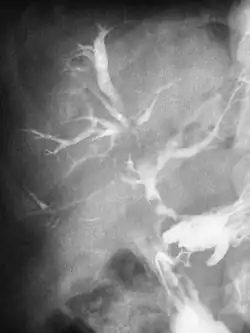

Although most fistulas are in forms of a tube, some can also have multiple branches.[9]